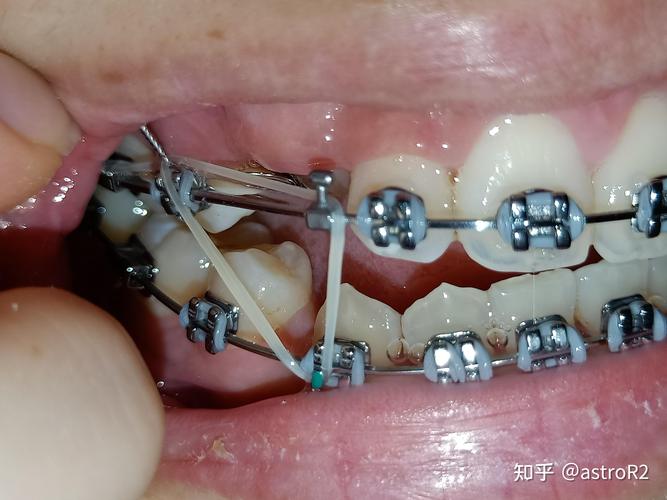

(图片来源网络,侵删)- 医生弯制/粘贴时位置不理想: 在弯制问号钩或将其粘贴在牙齿上时,如果位置稍微偏离理想位置,或者角度不合适,其末端或凸起部分就可能直接压迫或摩擦到相邻的牙龈组织(牙肉)。

- 牙齿移动导致相对位置改变: 在矫正过程中,牙齿在持续移动,原本不压迫的问号钩,随着牙齿位置的变化,其末端或凸起部分可能逐渐靠近甚至顶住牙龈。